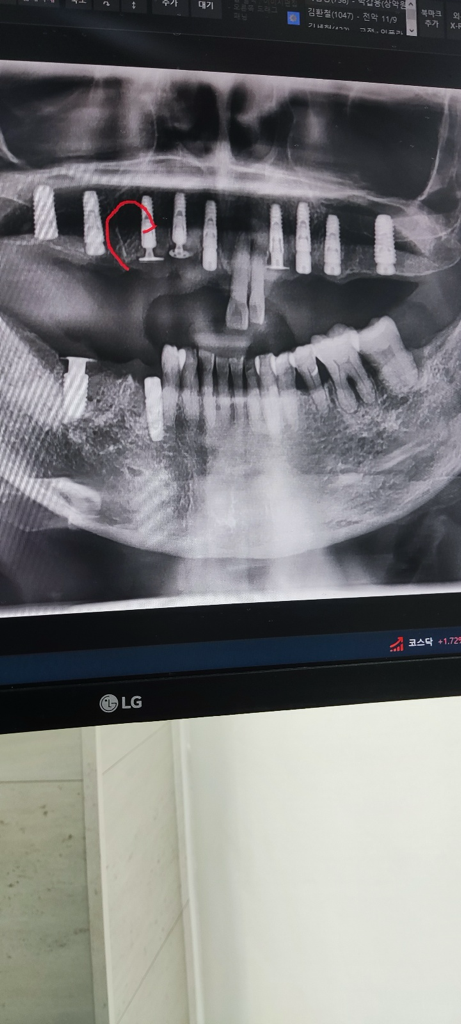

지난해 12월 11일에 윗쪽 앞니 3번과 우측 어금니 6번, 그리고 아랫니 6번에 뼈 이식을 했습니다. 치아는 아직 완성되지 않았고 대기 중입니다. 그런데 뼈 이식한 잇몸에서 뼈가 뾰족하게 나오고 만지면 통증이 있습니다. 돌출된 부분은 깎으면 된다고 하는데, 이대로 진행해도 되는지 걱정이 됩니다.

아래사진은 3개월전에 찍은 사진입니다

임플란트 자체의 문제보다는 임플란트를 감싸고 있는 뼈 부분에서 날카로운 부분이 있는 것으로 보여집니다. 2차 수술을 할때 해당 부분을 다듬어주면 큰 문제는 없어 보이나 정확한 판단을 위해서는 x-ray 사진이나 ct 등을 통해 평가가 필요해보입니다.